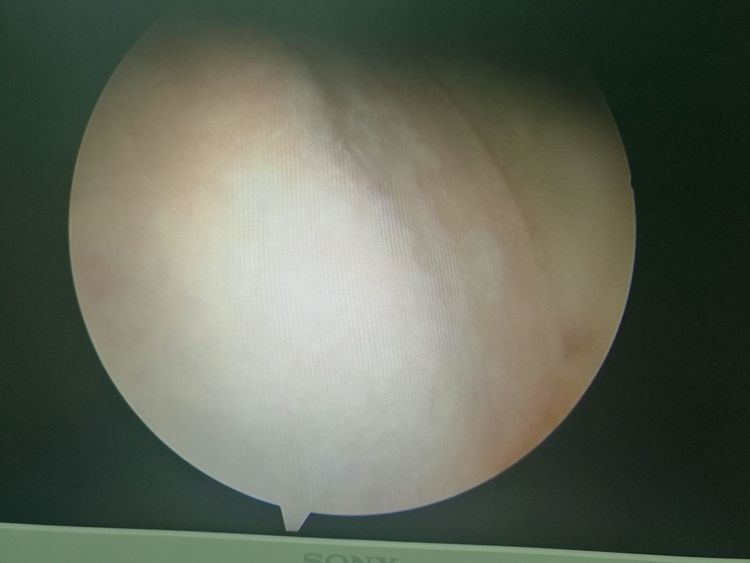

镜下手术图片,展示人体关节镜下情况:

骨科中心近两年共收治关节镜手术病人500余人,本人在近半年共收治关节疾病患者70余人,包括肩关节脱位及盂唇损伤、半月板损伤、交叉韧带损伤、叉韧带止点撕脱、髌骨脱位、色素性滑膜炎、关节游离体、老年骨性关节炎、踝关节外侧副韧带损伤伴距骨软骨损伤等。均通过关节镜或辅助关节镜手术治疗,短期内随访效果好,总体满意率在95%以上。